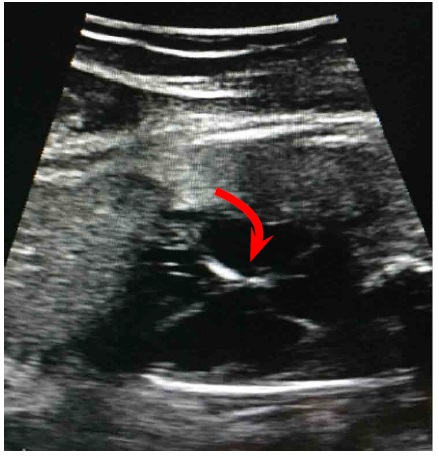

Al ingreso al HUCSR se realizan pruebas de bienestar fetal las cuales son normales; posteriormente se realiza ecografía de detalle en la cual no se observan signos de hidrops fetal ni otras alteraciones anatómicas. Finalmente, se realiza ecocardiograma fetal donde se encuentra situs solitus, situs vascular normal, eje cardiaco de 45º, relación cardiotorácica de 0,55, corte de cuatro cámaras normal, concordancia auriculoventricular y ventriculoarterial, inserción valvular normal, foramen oval permeable, flujo hacia aurícula izquierda, movimientos de paredes libres de ventrículos de amplitud normal; se observa imagen hiperecogénica a nivel del nodo sinoauricular sugestiva de fibroelastosis endocárdica (figura 1). No se evidencia ritmo sinusal, se documenta disociación auriculoventricular en Modo M ((figure 2), con frecuencia cardiaca ventricular de 50 lpm y frecuencia auricular de 135 lpm, segmentos PR variables, e istmo aórtico con flujo anterógrado. No hay evidencia de disfunción diastólica dada por ductus venoso normal.